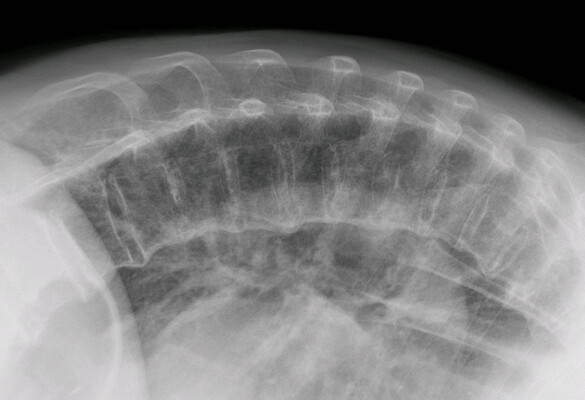

- The mutant mice and wild type littermates were treated with ISRIB or vehicle daily. Radiographic analyses revealed that the dwarfism was ameliorated, and the skeletal deformities were greatly improved by the treatment of ISRIB. Treatment of ISRIB also eases the abnormalities of intervertebral disc degeneration syndrome in the mutant lumbar spine, too.

- Figure 1